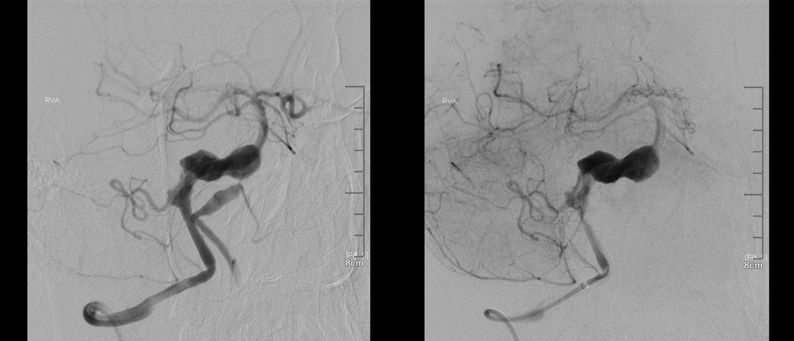

术前右椎动脉造影显示:基底动脉中下段夹层动脉瘤。

术前右椎动脉3D造影

术前左椎动脉造影显示:基底动脉中下段夹层动脉瘤,左侧小脑后下动脉夹层动脉瘤。